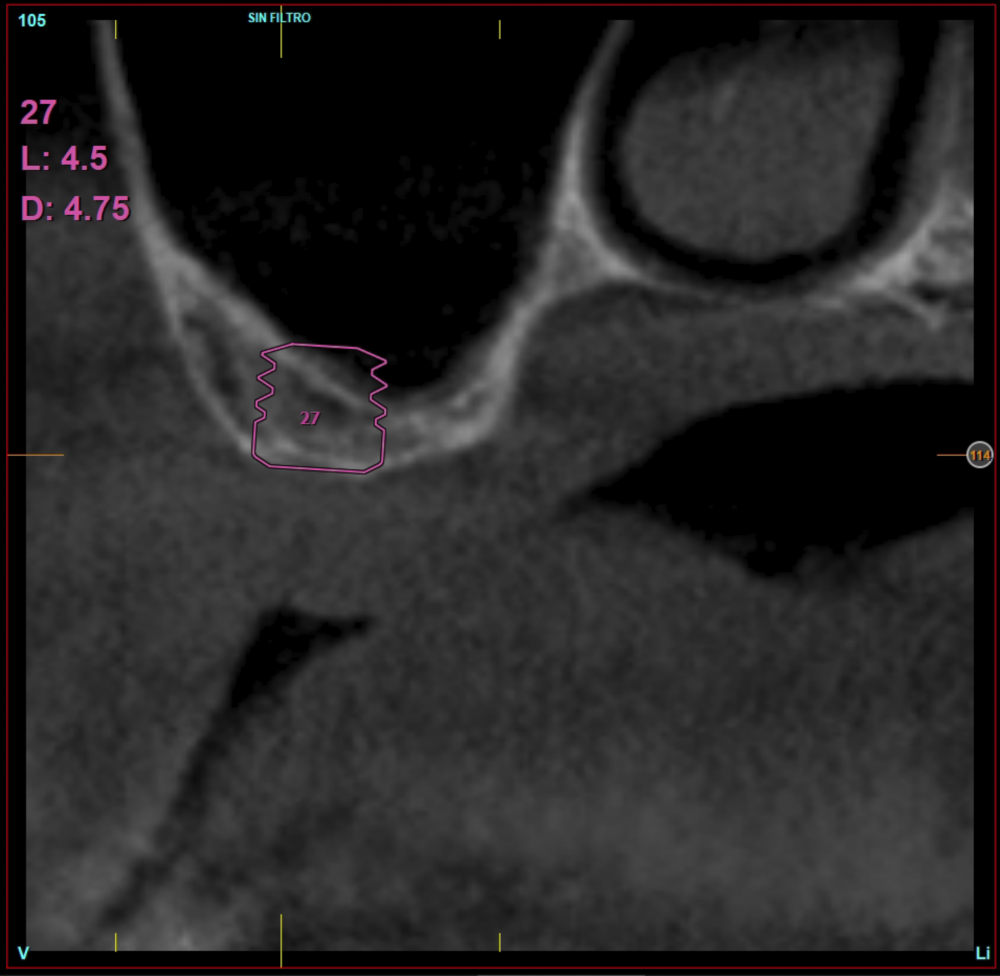

Ten patients who met the inclusion criteria were recruited, in which 20 implants were inserted. Three of them were women with an average age of 72 (+/- 6 years). None of the patients were smokers at the time of surgery and did not have any active periodontal disease. The majority of the implants diameter included in the study was 5 mm (60%), followed by 4.5, 5.5 and 4.75 mm (13.33% each). The predominant length was 5.5 mm (86.6% of the cases), with 13.4% of the remaining implants with a length of 4.5 mm. The most common positions were for the second molars (molars 27 and 17) representing 55% of the cases.

The mean height of the residual bone volume was 3.1 mm (+/- 0.3 mm with a range of 3-4 mm). In all cases, transcrestal sinus elevation was performed, with particulate autologous bone obtained from milling the neo alveolus generation zone for implant insertion, being the average of this elevation above the apex of the implant of 2.8 mm (+/- 0.99 range 1.9 -5 mm). In the CT control scan after one year of inserting the studied implants, the bone gain achieved was maintained, no decrease in the volume gained was observed, only three cases showed a decrease of between 0.4 and 0.5 mm of the initial volume at the end (Table).

Figures 2-19 show one of the cases included in the study.

In all cases, a diagnosis was made based on study models, intraoral examination of the patient and performing a Cone-beam analysed using the specific BTI-Scan 3 software (Biotechnology Institute, Vitoria, Alava, Spain).